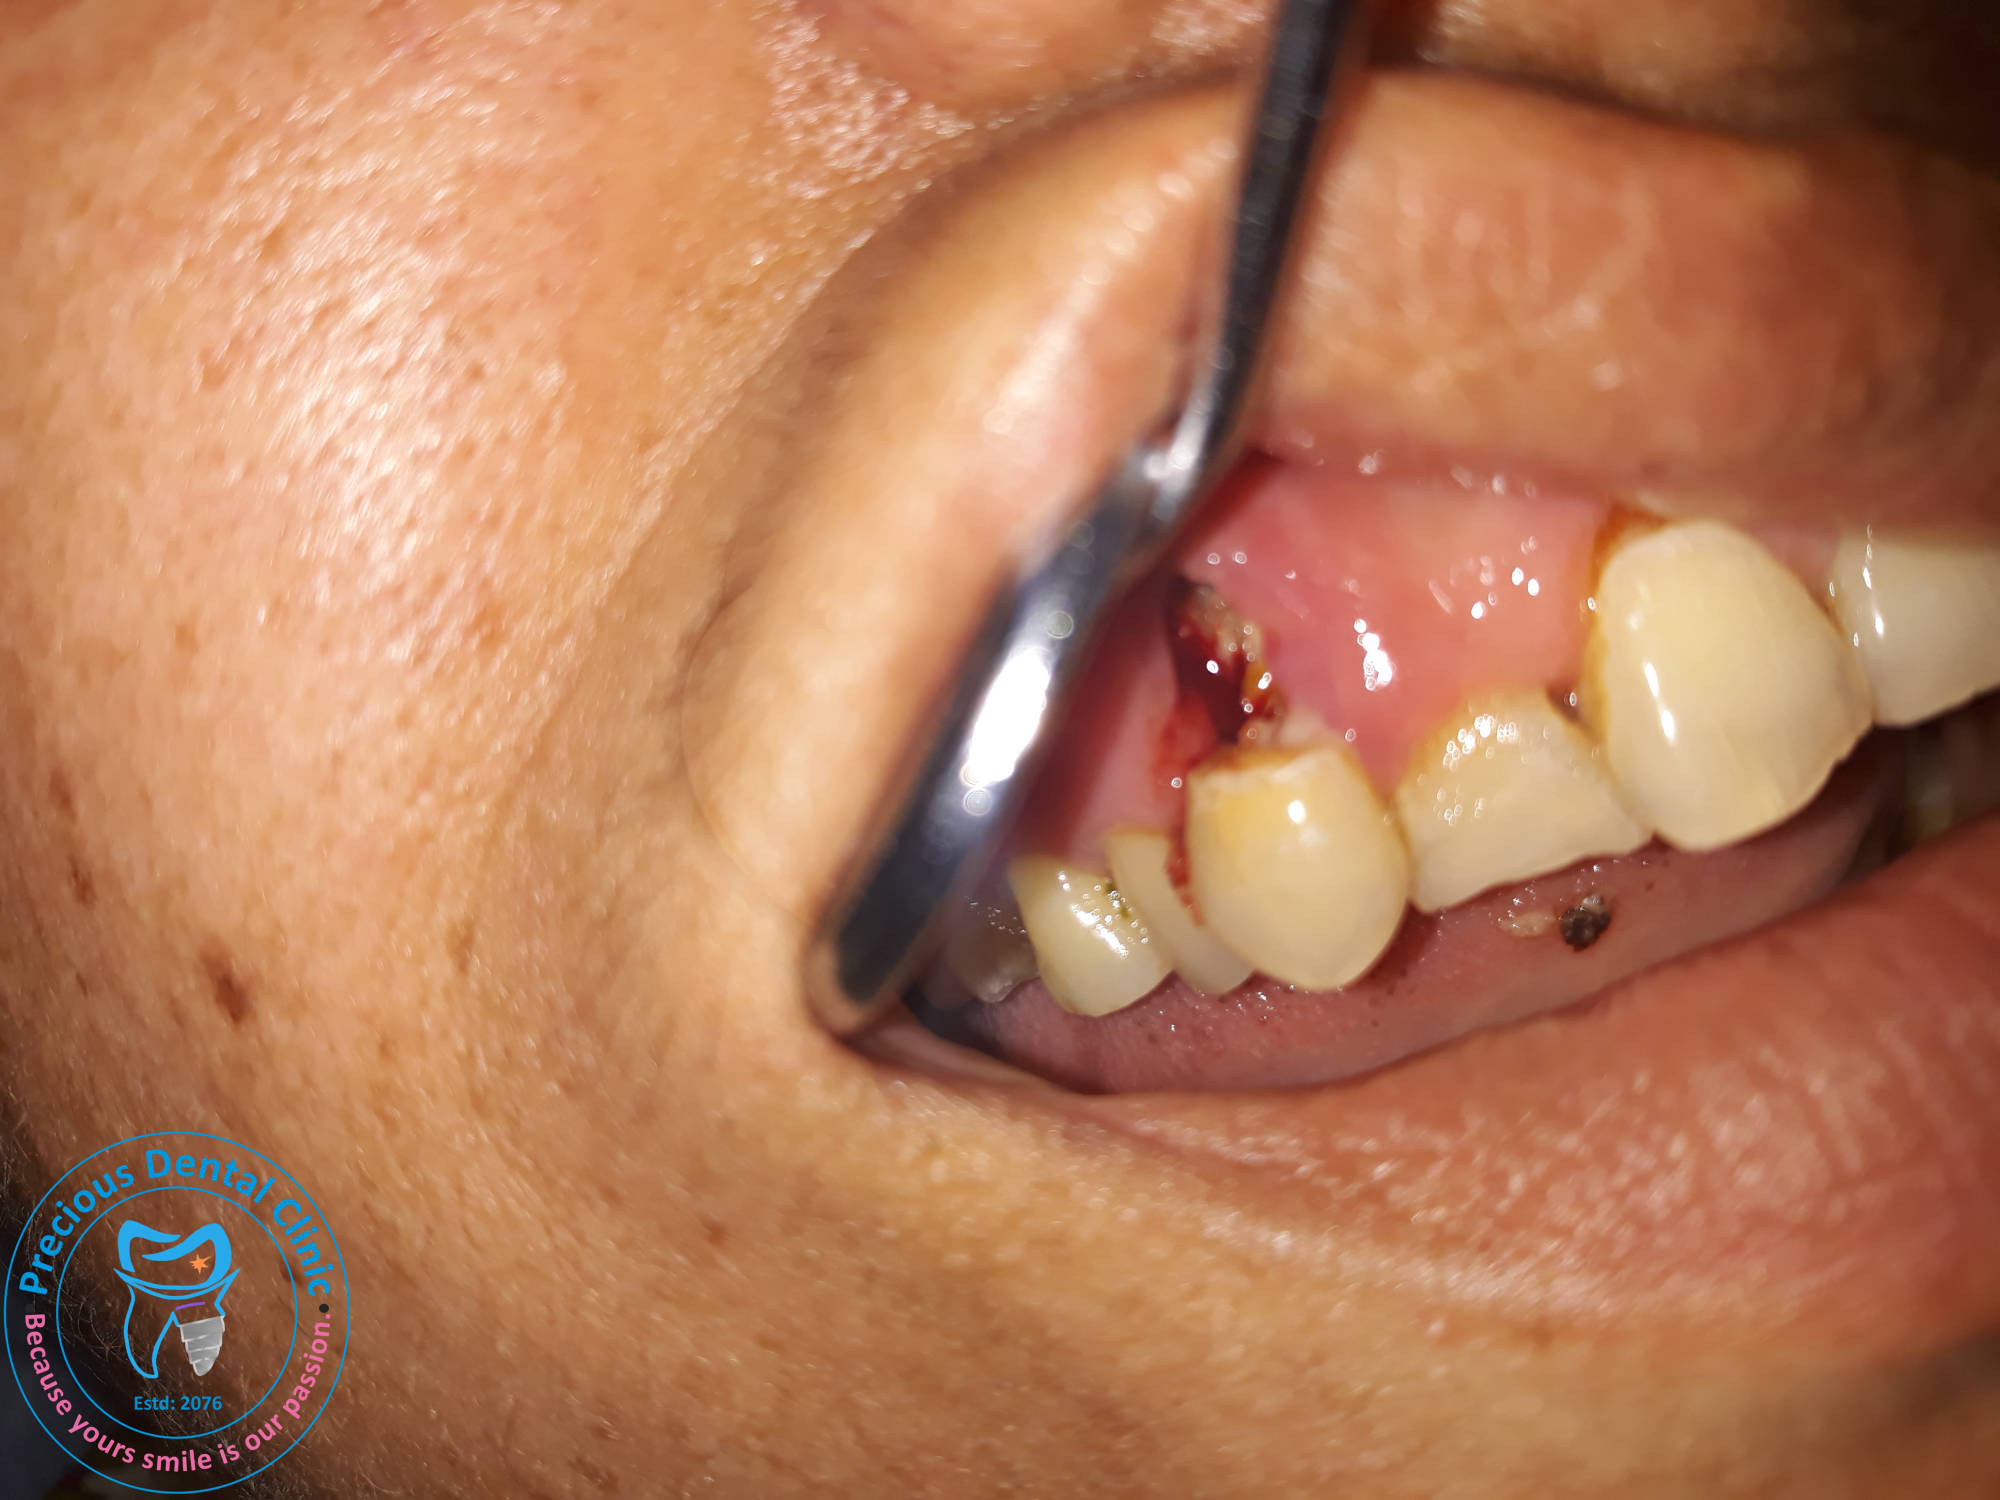

Collection of photos, here you will find the photos of doctor, services, environment and work.